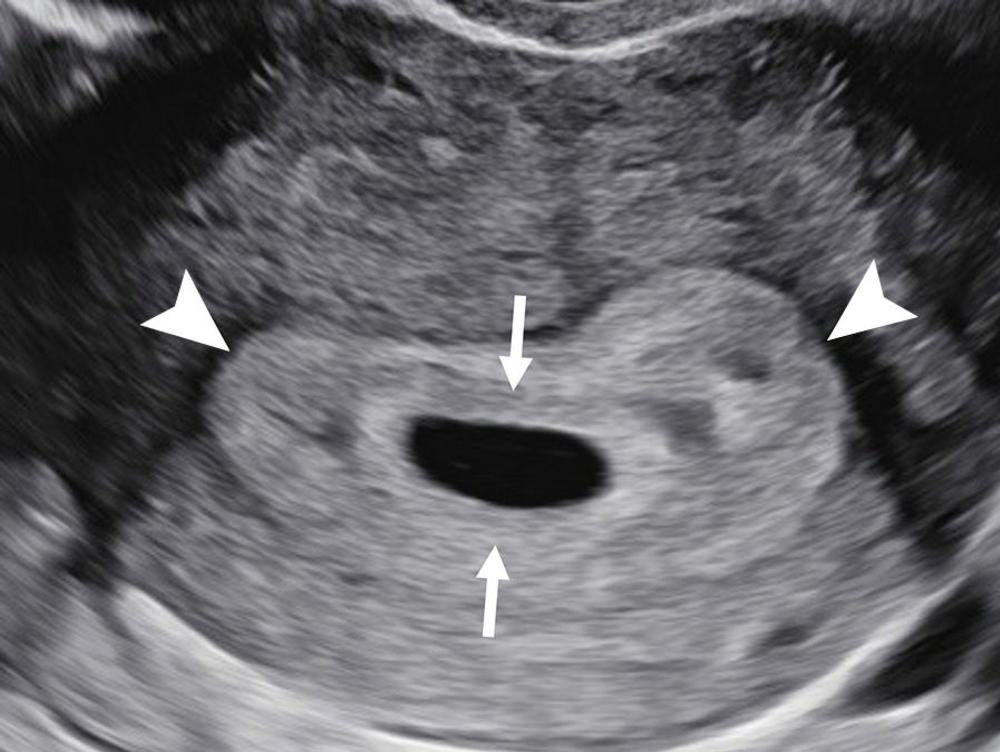

Figure 4. Double decidual sac sign. Transvaginal transverse grayscale US image in a 27-year-old pregnant patient at 5 weeks 3 days shows two concentric echogenic rings around an oval fluid collection representing the double decidual sac sign. The inner echogenic ring (arrows) corresponds to trophoblastic chorion and decidua capsularis. The outer echogenic ring (arrowheads) represents decidua vera and endometrial lining. The double decidual sac sign is more specific for an intrauterine pregnancy than the intradecidual sign when the gestational sac is empty.